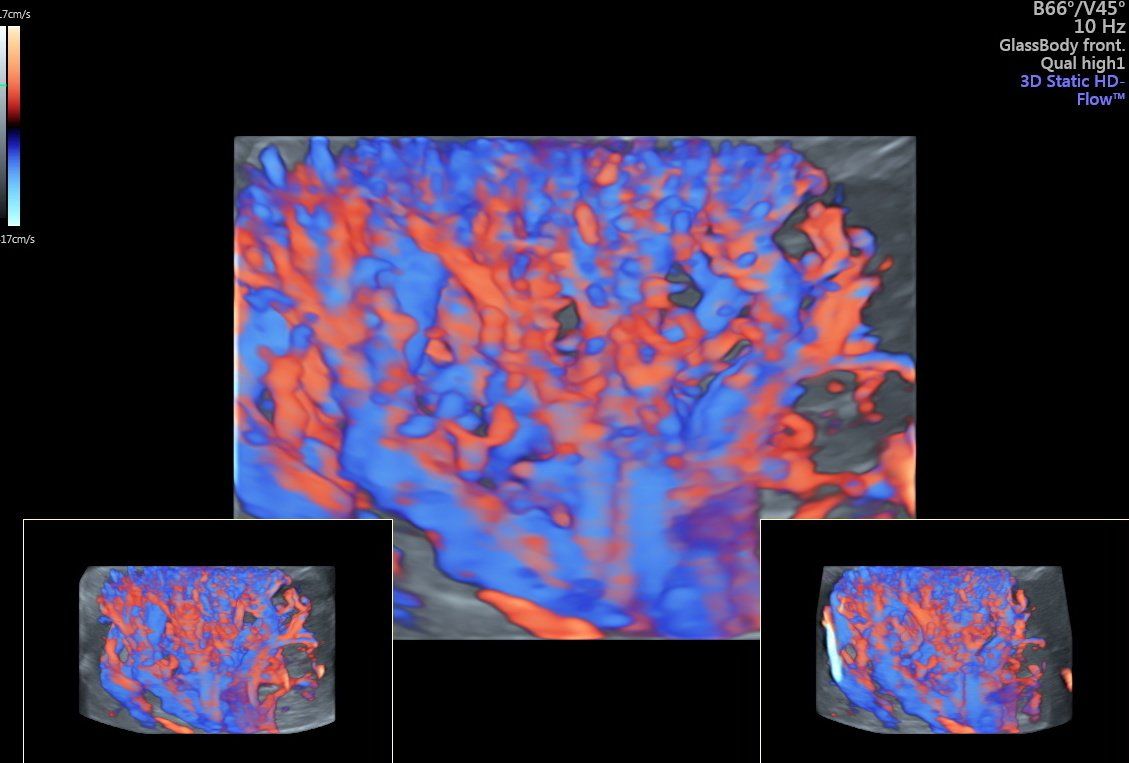

La diagnostica Eco-Color-Doppler si rende utile sia nello studio degli organi interni sia nella valutazione dei distretti vascolari arteriosi e venosi. Gli esami eco-color-Doppler sono indicati per lo studio delle carotidi/tronchi sovra-aortici (patologie cerebro-vascolari e cardiologiche), per la valutazione dell’aorta addominale (aneurismi, dissecazioni), per la valutazione delle arterie degli arti inferiori (arteriopatia ostruttiva, diabete), per la valutazione delle vene degli arti inferiori (insufficienza venosa, varici arti inferiori).